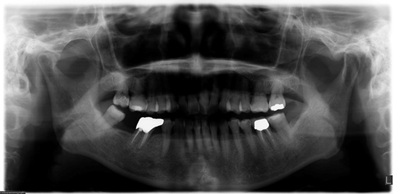

術前パノラマ![]() |

術前にはCT撮影を行い、骨の状態を精査した結果、骨量・骨質ともに良好であったため、歯ぐきを切開せずにインプラントを埋める「フラップレス術式」を採用しました。これにより、術後の腫れや痛みを最小限に抑えることができ、患者様の身体的負担を軽減することが可能となります。

使用したインプラントは、ストローマン社製のBL SLアクティブインプラント(直径4.1mm、長さ10mm)です。